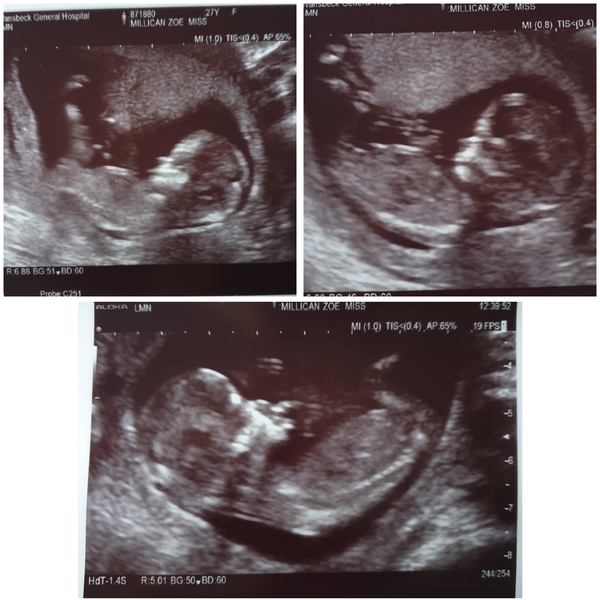

Zoey92 · 11/12/2019 14:51

Everything went fantastic! Baby was a right little wriggler & loved tucking his/her chin right in 😂 12w3d due 21st June.

All measurements looked good but took 3 attempts to take bloods 🤦‍♀️ x